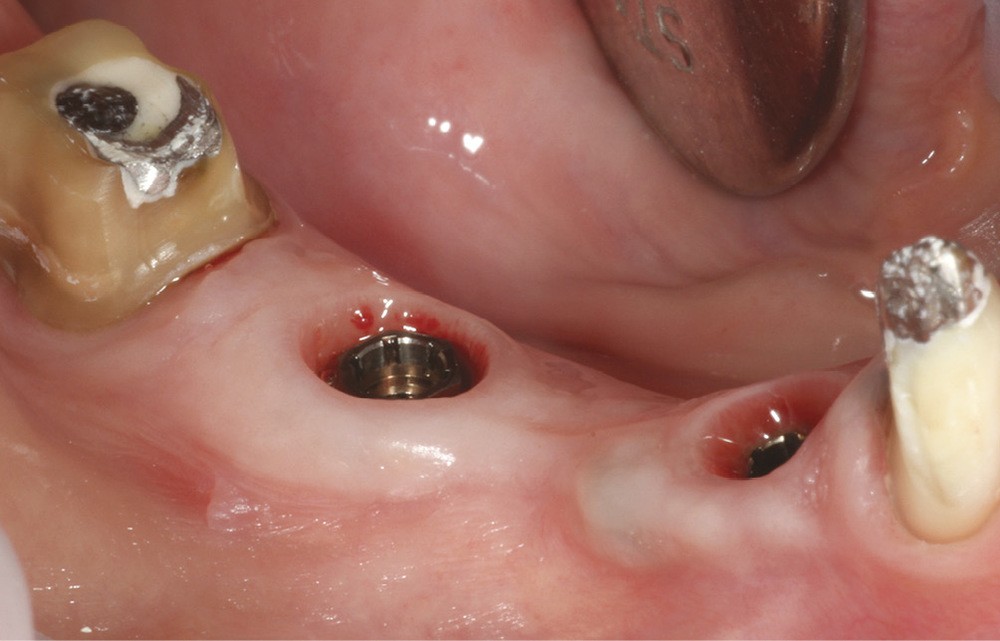

L’ostéointégration, bien maîtrisée à l’heure actuelle, ne constitue plus le seul critère définissant un « succès implantaire ». En effet, s’y ajoute la recherche d’une restauration prothétique intégrée au contexte gingivo-dentaire environnant, tant sur le plan esthétique que fonctionnel. Cela suppose tout d’abord une préservation maximale, voire une reconstruction, des tissus ostéo-muqueux péri-implantaires [1] ; puis, une approche prothétique adéquate. La littérature récente montre que les restaurations implantoportées fixées présentent une bonne longévité, celle-ci concernant aussi bien l’implant que la suprastructure, qu’elle soit unitaire ou plurale [2-4]. Le succès à court terme est grandement conditionné par la gestion de la zone transmuqueuse, qui doit à la fois mimer au mieux l’émergence naturelle de la dent pour assurer la persistance des papilles, mais aussi favoriser un environnement nettoyable et peu propice au développement du biofilm bactérien. À moyen et long terme, les aspects occlusaux, de même que les aspects mécaniques liés aux matériaux ou à l’assemblage deviennent prépondérants. Ainsi, le mode de connexion entre l’implant et la restauration prothétique sus-jacente (pilier ou couronne transvissée) impacte non seulement la stabilité de l’assemblage, mais aussi celle des tissus naturels environnants. Cet article se propose de faire le point sur les formes de connexions prothétiques existantes et sur l’impact de ces choix sur les plans biologiques et biomécaniques.

Les édifices implantaires comprennent tous une connexion entre l’implant lui-même, et l’(es) élément(s) prothétique(s). La forme et le positionnement spatial de l’implant au niveau de cette jonction (prothèse/implant) définissent le type de la connexion.